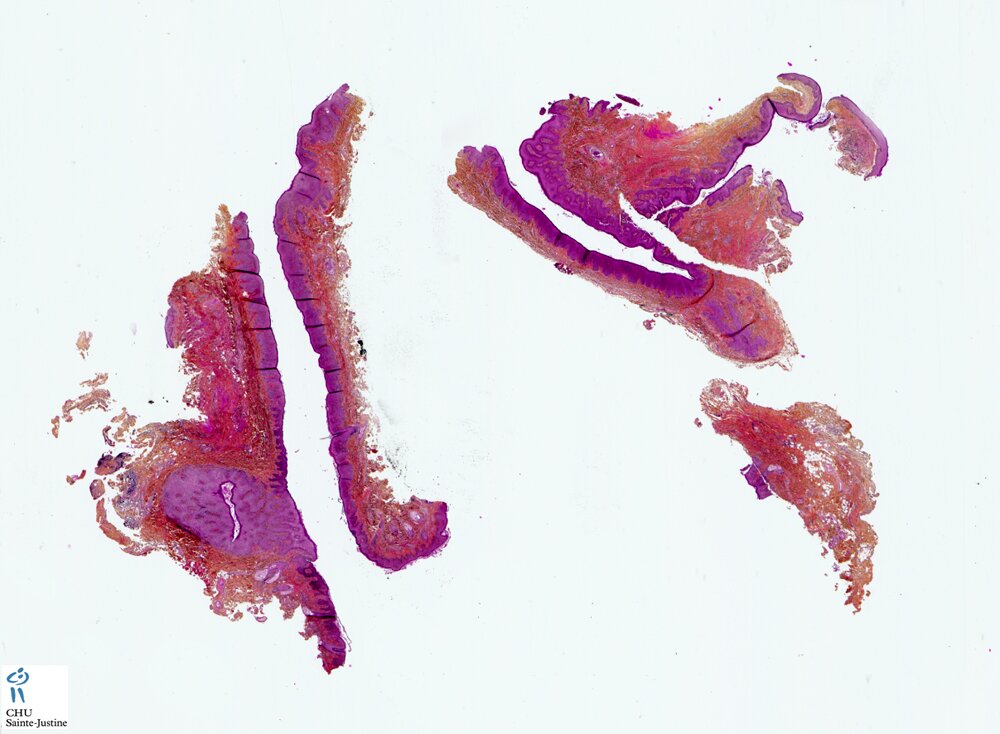

branchial fistula

Preauricular branchial fistula

- preauricular branchial fistula